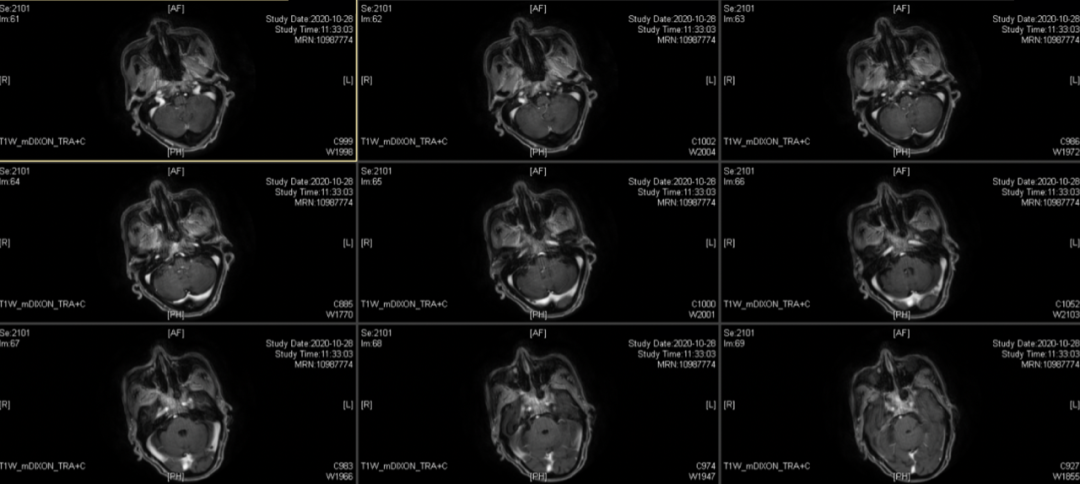

影像学检查:鼻咽部双侧壁粘膜稍增厚,未见明确异常结节及肿块征象。鞍底、双侧蝶窦壁、斜坡、双侧枕骨髁及岩尖骨质破坏,考虑放射性骨损伤可能。

2020-10-28上腹部MRI:肝S2段转移瘤

肝S2段内见一长T2 长T1信号,边界清,约42mm*31mm,增强后呈环形强化,弥散受限。考虑转移瘤。

放疗结束MR报告:2021-1-9PET-MR示“鼻咽部黏膜增厚伴糖代谢增高,考虑肿瘤治疗后部分活性残留,枕骨斜坡、蝶骨体及梨骨后缘骨质破坏合并糖代谢增高,考虑肿瘤活性残留;双侧颈部未见高代谢淋巴转移影像改变;肝左叶S2结节伴糖代谢局灶性增高,考虑转移瘤”。

鼻咽部肿物活检,疑恶性肿瘤,予加做免疫组化,结果示炎症性改变、原位杂交示EBER个别淋巴细胞+。